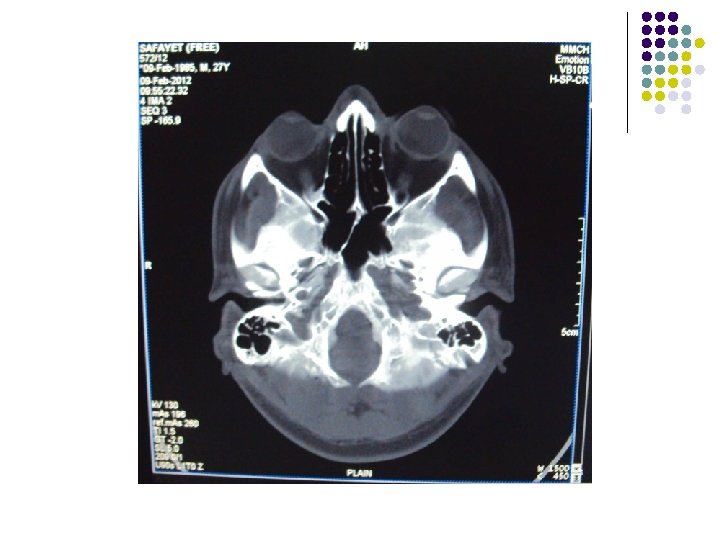

CT Scan of Brain

Clinical Diagnosis Retrobulbar solid tumour on left orbit